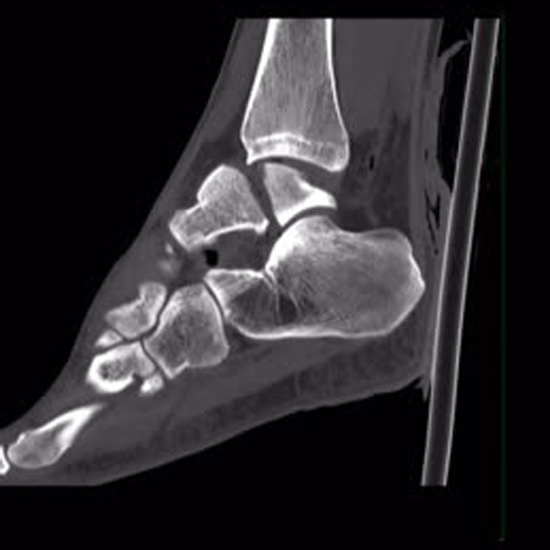

CECT (Contrast Enhanced Computed Tomography) Left Ankle Joint is an imaging procedure used to visualize the problems in the left ankle joint. The doctor recommends this scan to evaluate the left ankle joint regions for fracture, injuries, infection, inflammation and other disorders if it’s not visible in the X-ray. The radiologist will inject you with contrast media and use a rotating x-ray beam to obtain pictures of the left ankle joint.

CECT scan for ankle joint is a diagnostic imaging procedure that helps your doctor to visualize any problems occcuing in your left ankle joint including infections, fracture, injuries, inflammation, or other disorders. The scan is conducted using a contrast media that helps in obtaining mre enhanced and clear pictures of the ankle joint.

The CECT scan of ankle joint can help in treatment planning as a preoperative surgical protocol. The test helps in evaluation of deformities in peri-articular region or intra-articular region, including fractures. The scan can also show prosthesis loosening, periprosthetic fractures, and bony collapses that may result from avascular necrosis.

The CECT scan for the ankle joint contains a sensitivity of 83% and a specificity of 97% for extended knees; and a sensitivity of 86% and a specificity of 100% for flexed knees.